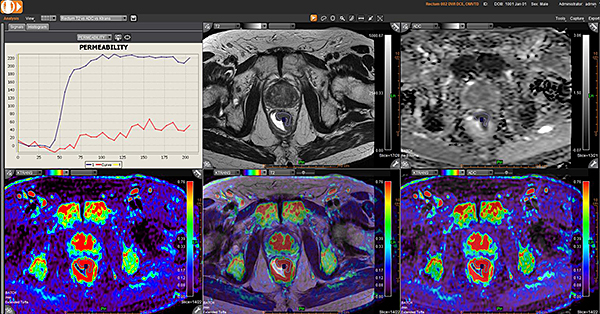

Додаток MR Prostate

Додаток MR Prostate інтегровано до розширеної візуалізації Vitrea. Він забезпечує виявлення, характеристику та стадіювання ураження.

Забезпечує миттєву комплексну оцінку ураження та високоякісну оцінку дифузії

Дає змістовну звітність, включаючи локалізацію та об’єм ураження

Надає рекомендації PI-RADS V2 щодо стандартизації термінології і протоколу опису, а також уточнює ризик клінічно значущих пухлин